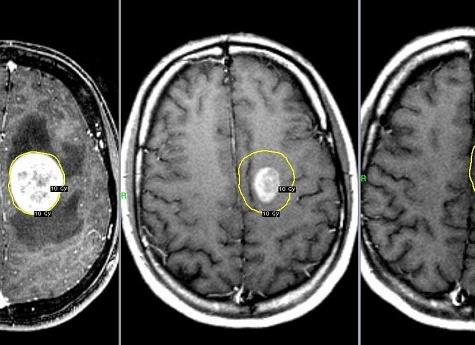

С помощью МРТ можно установить, есть ли в полости головы новообразования, раковые опухоли, кисты. Более того, с точностью до миллиметра определить их размер, охарактеризовать структуру. Для того чтобы узнать, насколько быстро растет опухоль, есть ли угроза жизни человека, разрушение мозговых тканей, проводится несколько обследований.

Расшифровка результатов

Снимки, поступающие на компьютер, в дальнейшем можно обрабатывать при помощи специальной программы. Благодаря тому, что мозговые ткани фотографируются под разными ракурсами, на выходе получают срезы головного мозга, из которых можно составить объемное изображение. Сравнивая фото здорового человека и больного, врач может увидеть отличия в состоянии тканей и поставить точный диагноз.

Например, если человек перенес геморрагический инсульт, в мозговых тканях образуется зона повышенной плотности, гематома, что может показать МРТ головного мозга. Кровоизлияние выглядит на снимках светлее здоровых тканей мозга.

При записи томограммы врач-радиолог, находящийся в соседнем кабинете, наблюдает на экранах изображение в виде послойных срезов головы в режиме реального времени. Таким образом, он может с точностью до миллиметров оценить расположение любых структур головного мозга и сделать заключение.